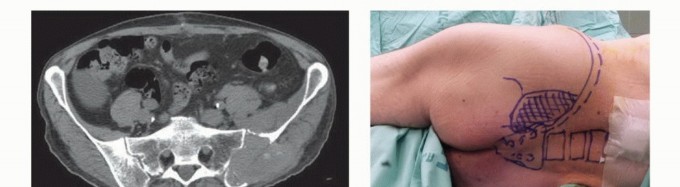

يُعد الأستاذ الدكتور محمد هطيف، بخبرته الواسعة التي تتجاوز 20 عامًا ودقته المتناهية في جراحة العظام، الرائد الأول في علاج نقائل الحوض في صنعاء واليمن. بصفته أستاذًا في جامعة صنعاء، يتبنى الدكتور هطيف منهجًا شاملاً يركز على استعادة وظيفة المريض وتخفيف الألم وتحسين نوعية حياته، باستخدام أحدث التقنيات الجراحية وأفضل الممارسات العالمية. يُدرك الدكتور هطيف أن الأورام اللحمية الأولية والأورام النقائلية غالبًا ما تتمدد بشكل كبير إلى الأنسجة الرخوة المحيطة، ولكن نظرًا لحساسيتها المتأصلة للعلاج الإشعاعي، فإن الإدارة الجراحية للآفات النقائلية لا تتطلب بالضرورة استئصالًا كاملاً للعضلات المغطية، حيث يمكن معالجة البقايا المجهرية بالإشعاع المساعد بعد الجراحة. يتطلب التشريح المعقد للحوض تخطيطًا تفصيليًا قبل الجراحة، وتحديدًا لتقنية التعرض وإعادة البناء، وتنفيذًا دقيقًا ومتقنًا للإجراء الجراحي لضمان أفضل النتائج للمريض.

- التصوير المقطعي المحوسب (CT Scan): يوفر صورًا مقطعية مفصلة للعظام والأنسجة الرخوة، ويساعد في تحديد حجم الورم، مدى انتشاره داخل العظم، وعلاقته بالهياكل المحيطة.